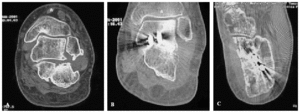

Figura 2. Paciente que tras una caída desde 4 metros de altura sufrió una fractura intraarticular de calcáneo, tratada con reducción cerrada. A: imagen coronal de tomografía axial computarizada (TAC) en la que se muestra la fractura intraarticular del calcáneo mal consolidada, disminución del espacio submaleolar externo y una importante exostosis lateral. B: imagen postoperatoria del mismo paciente en la que se ve la perfecta fusión subastragalina, y la descompresión del espacio submaleolar externo. C: imagen transversal de TAC, con una correcta alineación del calcáneo después de osteotomía de Dwyer, descompresión de la calcáneo-cuboidea y resección de la exostosis lateral, consiguiendo una buena alineación del calcáneo y descompresión lateral.